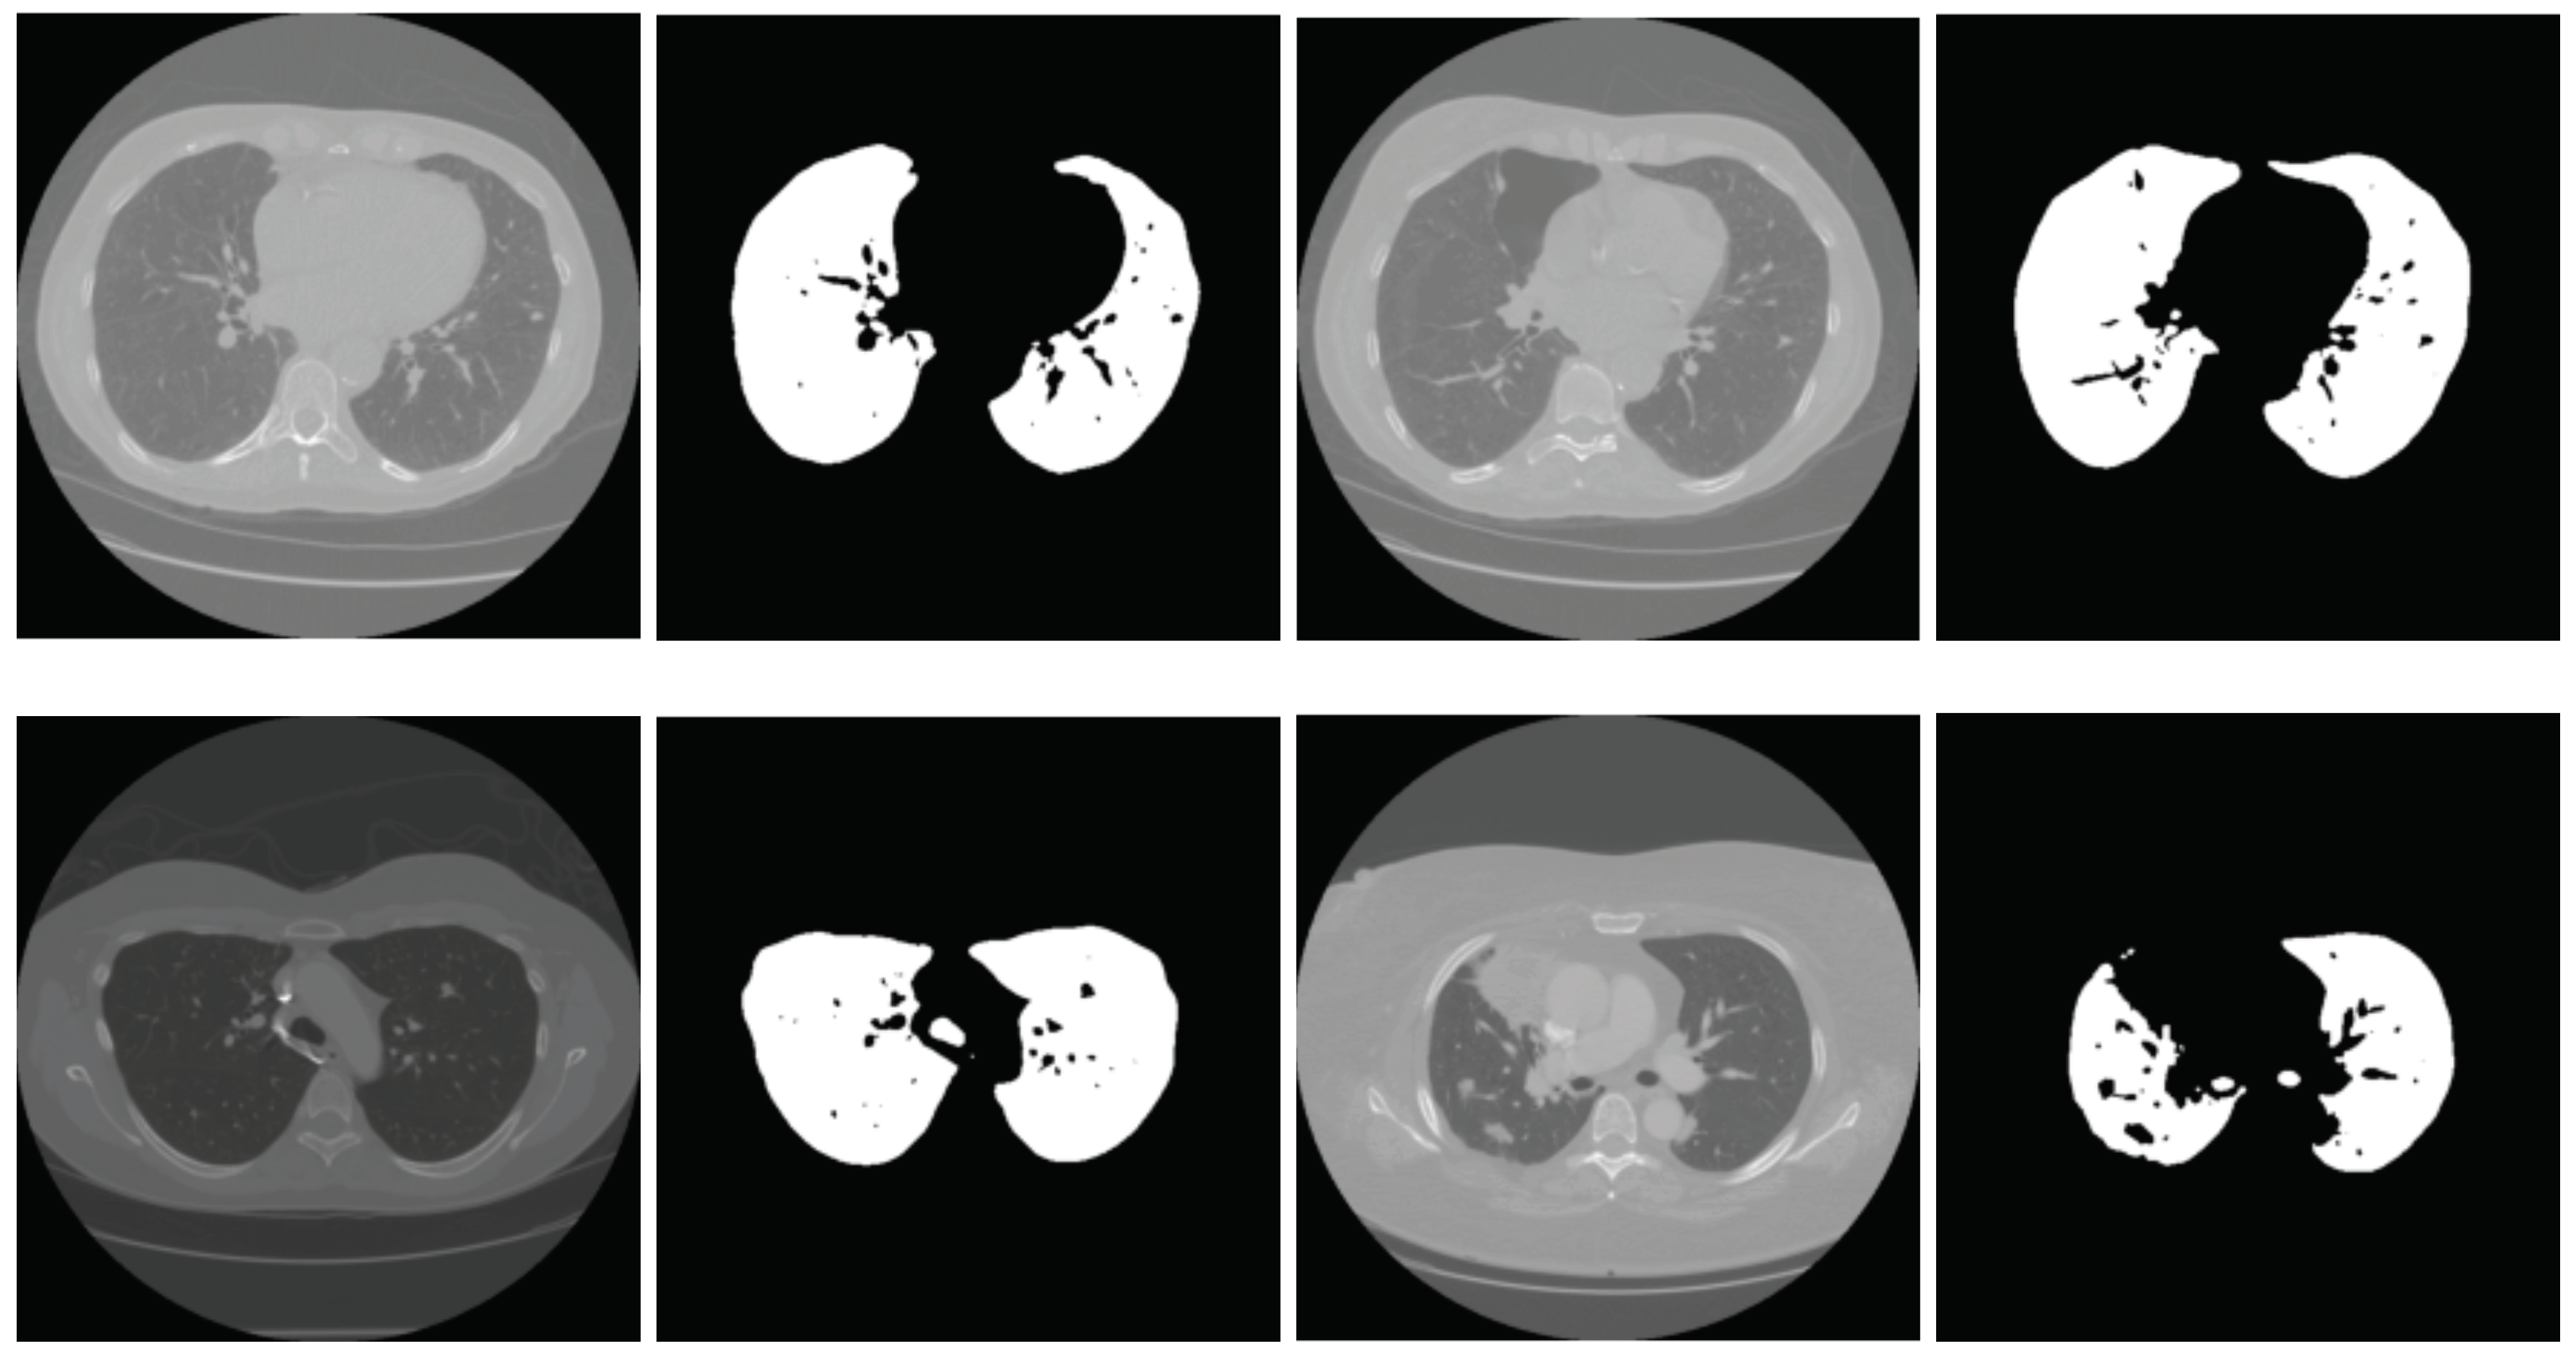

This mean serves as a better threshold than that estimated with the Otsu method in many cases; however, it still can suffer from bias toward the larger part. Specifically, if there is a significant number of large values (gray) compared to the background (black), the mean can be found in a similar region to the Otsu threshold. In Figure 6, we present some results obtained using the global threshold for lung extraction. The top two rows show the results where segmentation using global-mean-based thresholding produced good results, and the bottom two rows show some failure cases.

Figure 6.

The top two rows show a few examples where the segmentation using the global threshold is successful, and the bottom two rows show some examples where the method fails. In each pair, the left is the test image and the right is the segmentation result.

Since the threshold is taken as the average of the two local means, it overcomes the bias issue. In Figure 7, we present a few examples where the global mean thresholding technique produced poor results and the local mean thresholding produced () quite accurate results. From these lung images, it can be noted that a few lung pixels are incorrectly marked as non-lung and vice versa. To recover these pixels, we employ the watershed algorithm [39,40]. The obtained lung mask is used as the seed for the watershed algorithm. The third column in Figure 7 shows the result after applying the watershed algorithm. The resulting images present accurate lung segmentation.

Figure 7.

(a) Segmentation results using the global mean as the threshold, (b) segmentation results of the same images using the local mean threshold, (c) segmentation results after applying the watershed-based refinement.